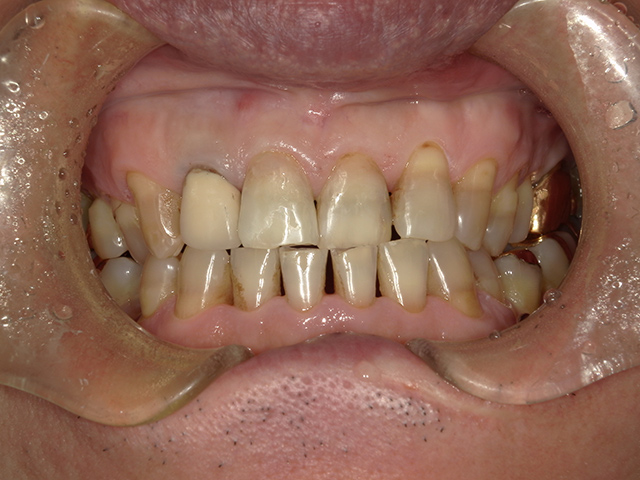

ダイレクトボンディングとは、高品質なレジン(樹脂)を直接歯に盛り付け、形や色を1本1本丁寧にデザインする審美修復治療です。

歯をほとんど削らない

従来のセラミック修復と比べ、削る量を最小限に抑えられます。(全く削らない症例もあります)

「できるだけ歯を削りたくない」「神経を残したい」という方に最適です。

すきっ歯・欠けた歯の修復に最適

そのため、症例によっては矯正治療やセラミック治療との併用をご提案することもあります。